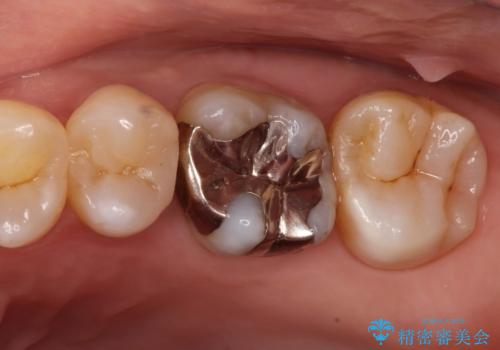

- 矯正終了後にメタルフリーの治療を希望された患者様です。

セラミックインレーにて修復治療を行なっております。